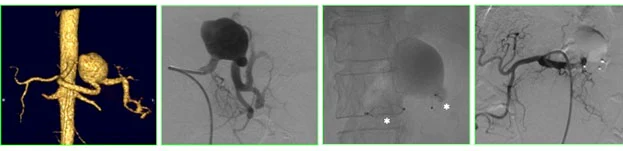

Un aneurisma è la dilatazione patologica di una arteria viscerale con un diametro almeno 1.5 volte superiore a quello normale, che interessa tutti i suoi strati. Questo fenomeno può essere pericoloso, a causa del rischio di rottura.

Uno pseudo aneurisma è una dilatazione dell’arteria che coinvolge solo uno strato del vaso, tipicamente a seguito di un trauma che danneggia l’arteria. In questo caso, il sangue fuoriesce dal vaso e viene contenuto solo parzialmente.

Le arterie splenica e epatica sono le più comunemente interessate da aneurismi viscerali. In particolare, l’arteria splenica è coinvolta nel 60-70% dei casi, mentre l’arteria epatica rappresenta circa il 20% degli aneurismi viscerali.